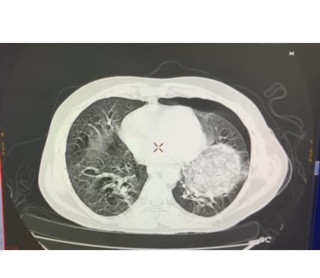

Fungal infections in the post renal transplant scenario are not uncommon, Mucormycosis is one such fungal infection which is agressive and life threatening. We would like to present our experience in post transplant patients with Mucormycosis. We observed 6 cases of Mucor over the past 6 years wherein 344 transplants were performed. Of the 6 -2 were Rhino cerebral mucor, 1 orbito rhinocerebral, and the rest were pulmonary mucor. Surgical interventions were taken up for 5 cases along with Liposomal Amphotericin B and posaconazole if required. Despite this agressive treatment we lost 4 patients with only 2 surviving.We observed all the patients who had Mucor recieved induction immunosupression with ATG and the onset of infection coincided with leucopenia.